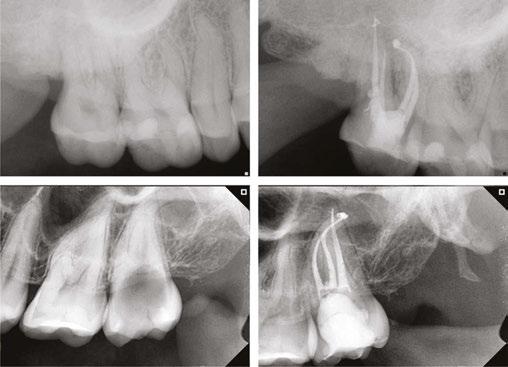

Clinical case performed by Dr. Benedict Bachstein (Figures 1-3)

The patient was diagnosed with irreversible pulpitis in tooth number 14, which presented multiple canals with highly complex anatomies. All canals were instrumented to 25/.04 and cleaned with Odne®Clean following the recommended clinical protocol. The use of Odne®Clean enabled the identification of five canal orifices and clearing of apical deltas.

Clinical case performed by Dr. Brett Gilbert (Figures 4 and 5)

In this case, Dr. Gilbert was initially unable to locate the MB2 canal, despite thorough attempts using ultrasonic and a microscope. After performing the irrigation protocol with Odne®Clean, the MB2 became visible. Following activation, the filling material extended completely through the MB2.

Clinical case performed by Dr. Sameer Jain (Figures 6 and 7)

The RCT involved a deep split tri-furcated premolar. Use of Odne®Clean enabled access to the advanced canal anatomy.